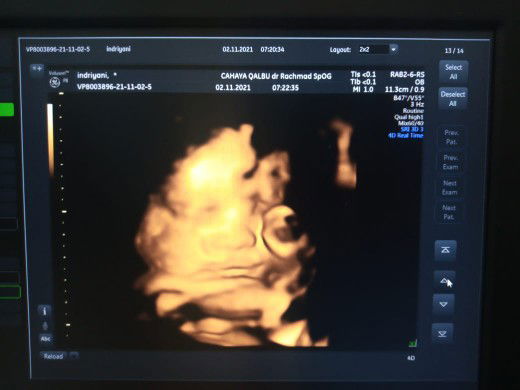

Baca lagiusg pastiin berat janin biar tenang.. ukuran perut ngak usah d masalahin & ngak bisa jaminan bbj juga.. banyak2 baca tntang kehamilan...

perut Bukan PATOKAN KEHAMILAN ya mbaa. yg penting bbj sehat sesuai usia itu cukup. kontrol rutin biar bisa pantau perkembangan janin

ya ga kenapa kenapaaa huhuhu usg rutin makanya ya buuk biar tau janin nya didalem apa kabar, jd ga mikirin ukuran perut terus